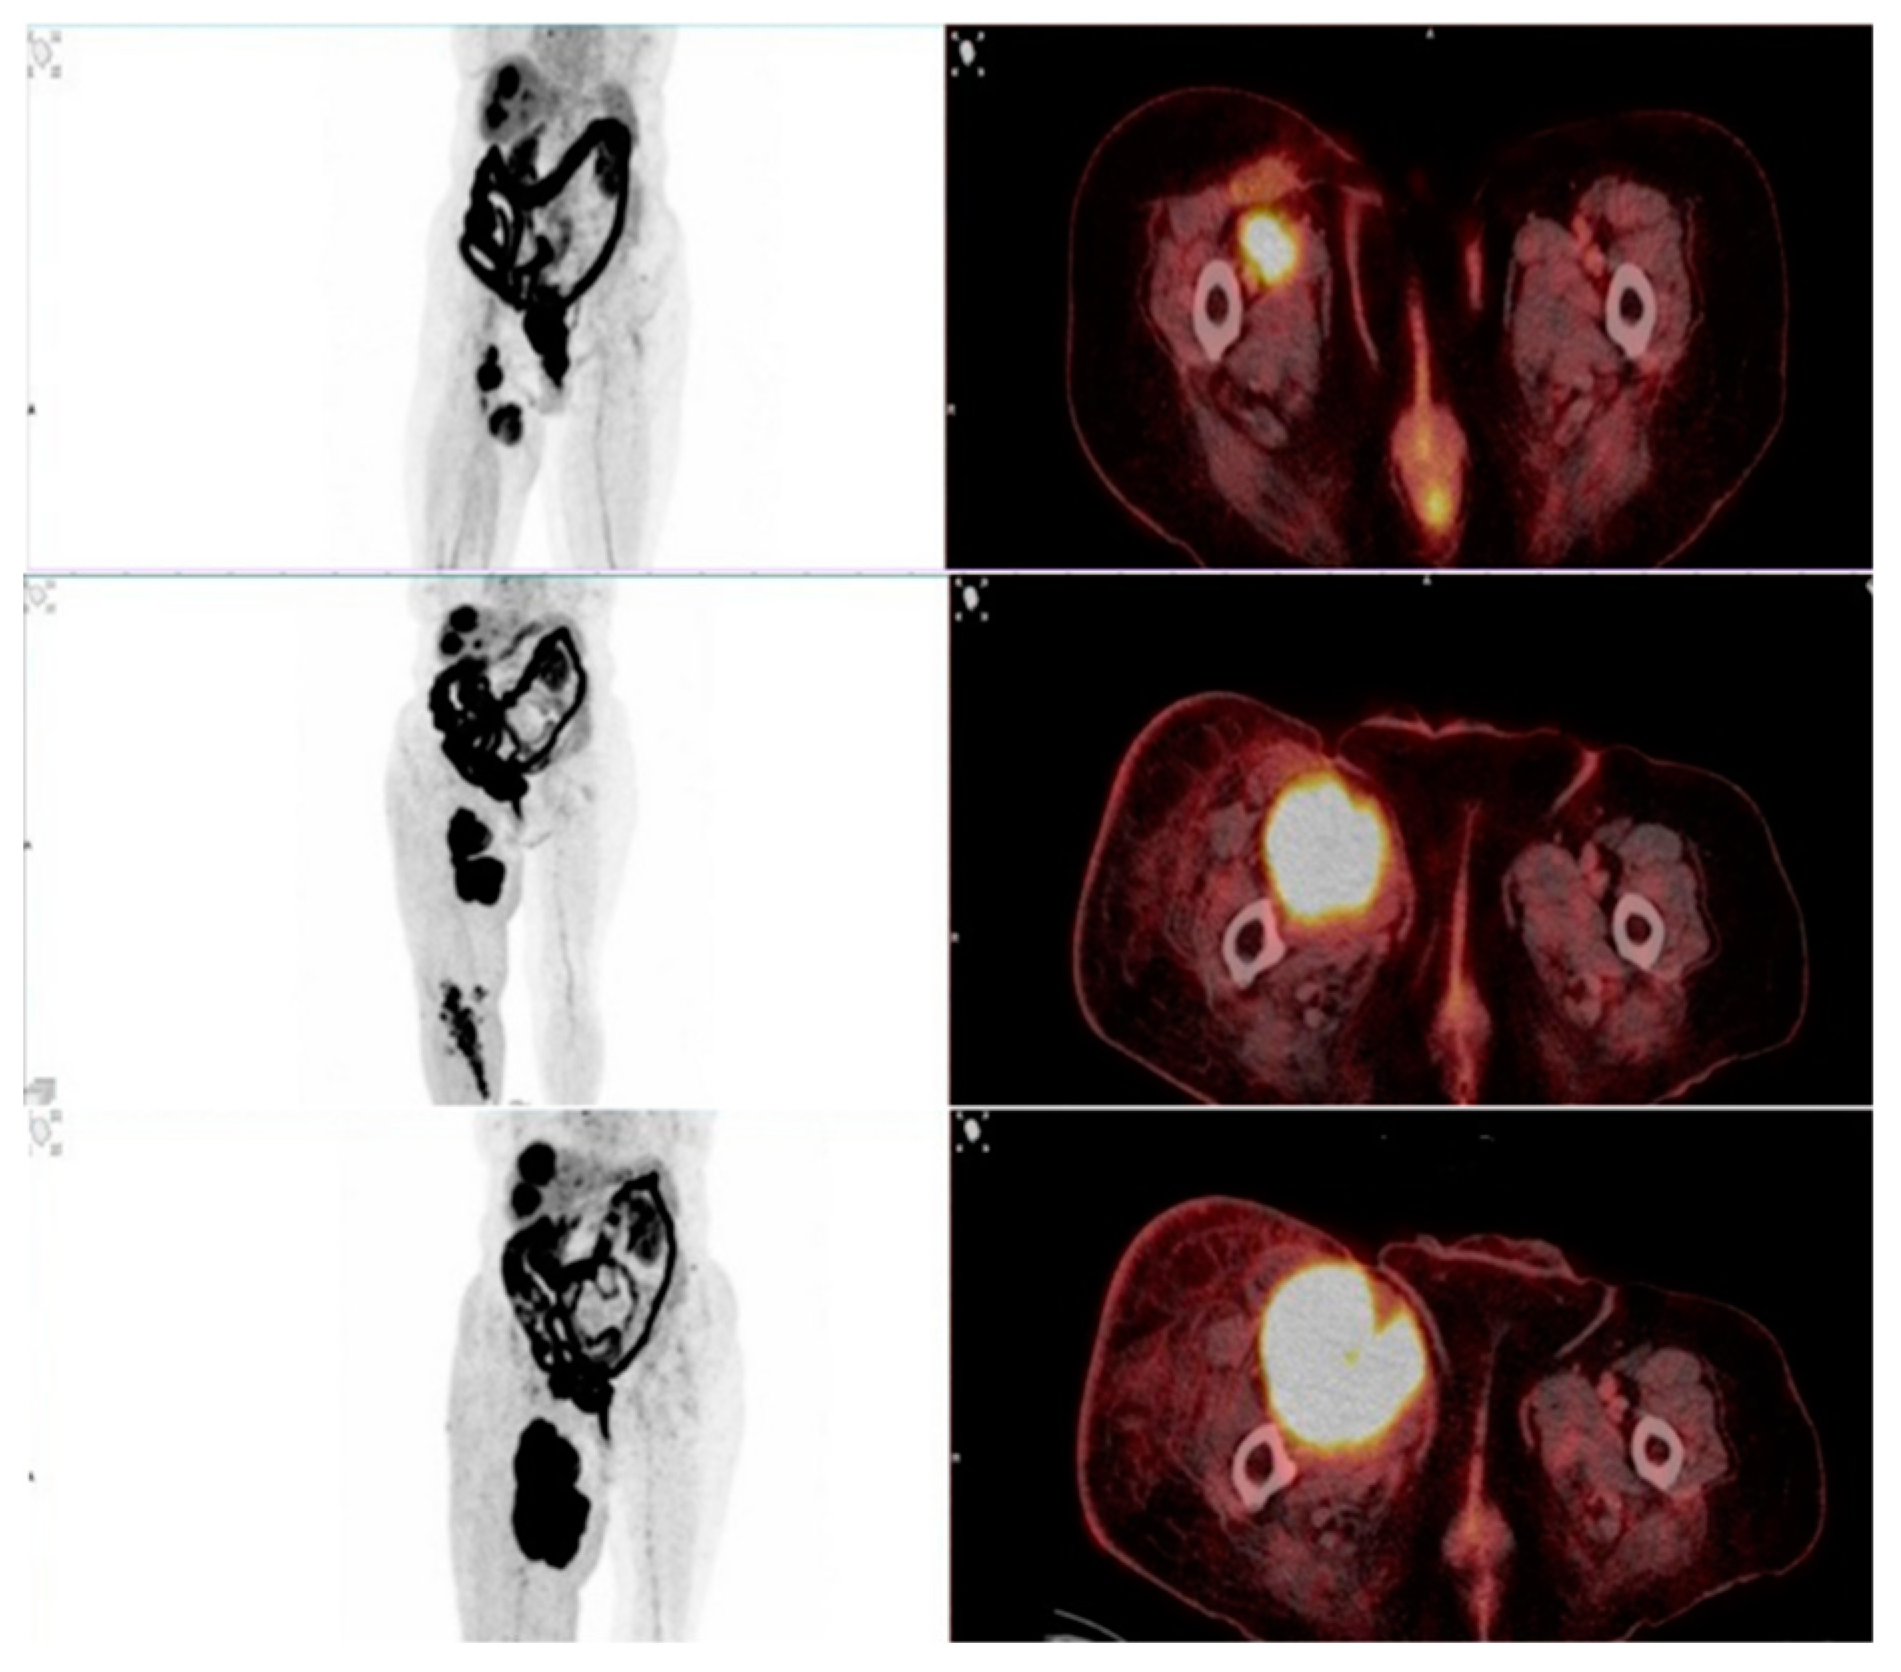

This study evaluated the role of F-18 FDG PET/CT in assessing therapy response in patients undergoing immunotherapy with immune checkpoint inhibitors (ICIs). One of the key findings was the ability of PET/CT to differentiate true progressive disease from pseudoprogression, which remains a major challenge in immunotherapy monitoring. Among the 93 patients, 9 showed stable disease (SD) or partial response (PR) on the required follow-up scans after 6–8 weeks and were therefore classified as pseudoprogression (Figure 4 and Figure 5). The estimated pseudoprogression incidence in our study – 9,7% - aligns with previously reported data. A systematic review and meta-analysis by Park et al. found an overall pseudoprogression incidence of 6% and less than 10%, with slight differences between cancer types, administered ICI and differences coming from the different definitions of pseudoprogression [33]. These results further support our findings and confirm that pseudoprogression remains a relatively rare, but clinically significant phenomenon. Failing to correctly identify pseudoprogression may result in the premature discontinuation of a beneficial therapy, depriving patients of a potential long-term response.

Figure 5. A case of true progression. Female with metastatic melanoma undergoing first line of immunotherapy showed increased size and metabolic activity in the primary tumor mass on the right leg on the first follow-up scan. ICI drug was not discontinued. 7 weeks later the second follow-up scan showed further increase in tumor burden. Therapy regimen was changed.